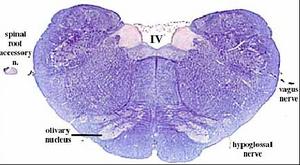

secciones transversales a diferentes niveles del tronco del encéfalo mostrando la localización de los núcleos neuronales eferentes de los nervios craneales

EFERENTES:

somatoeferentes (SE) : inervan músculos esqueléticos

visceroeferentes(VE): parasimpáticos